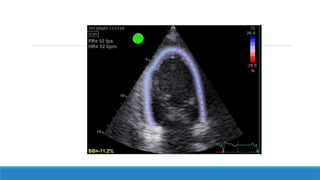

Techniques d’acquisition des images

Etape 1:

Obtenir des images de l’oreillette gauche en 4 cavités.

57

Etape 2:

Un traçage des contours endocardiques de l’oreillette gauche est réalisé

manuellement par l’opérateur et les contours épicardiques sont tracés

automatiquement par le logiciel, ainsi; une zone d’intérêt est crée.

58

Etape 3:

La paroi de l’oreillette gauche est divisée en 6 segments et le logiciel fait valider ou

non la zone de traçage réalisé pour chaque segment, une fois tous les segments sont

validés, la zone d’intérêt est approuvée et l’étude peut être réalisée.

Termes spécifiques pour l’étude de l’OG:

 PALS = LA strain reservoir («Peak Atrial Longitudinal Strain»). Il s’agit du pic positif de

l’étirement maximal de l’OG en télésystole lors de la phase de «réservoir». Il s’exprime en

pourcentage par rapport à l’état de base de l’OG.

 PACS = LA strain contraction («Peak Atrial Contraction Strain»). Il s’agit du raccourcissement

des fibres atriales gauches (exprimé en pourcentage) secondaire à la contraction atriale.

 LA strain conduit